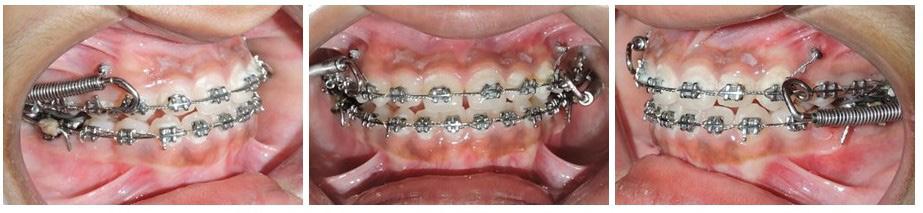

investigator and a total of 06 skeletal, 11 dental, and 03 soft tissue parameters were measured. Selected patients were also subjected to Acoustic pharyngometry (AP) for a three-dimensional evaluation of the upper airway. Fixed orthodontic appliance (022” MBT PEA) was bonded on both maxillary and mandibular arch, with banding of first & second molars. A standard wire sequence was followed till the full slot engagement with SS wire (19 X 25”) was achieved. A complete set of records were made to register the beginning of the fixed functional phase (T1) (Figure 2). Forsus appliance (FFRD) was fitted for each patient, push rod hooked on the archwire between canine and 1st premolar in the maxillary arch and distal end of open coil spring connected with the ‘L’ pin to the 1st mandibular molar. Maxillary and mandibular components of the Forsus FRD were connected to provide a forward thrush to the maxilla and a backward thrust to the mandible during the closure of the mouth (Figure 3). The functional phase with Forsus FRD continued till the desired objectives were achieved i.e., achieving positive overjet as well as satisfactory improvement in soft tissue profile.

To enhance the skeletal effects of the Forsus appliance, the indirect anchorage was obtained using TADs (temporary anchorage devices), placed in the maxillary arch, distal to canine. Post-functional records were made after the removal of Forsus FRD (T2) (Figure 4). Fixed orthodontic therapy continued to settle the occlusion and patients were debonded (Figure 5).

Figure 3: Forsus appliance in situ